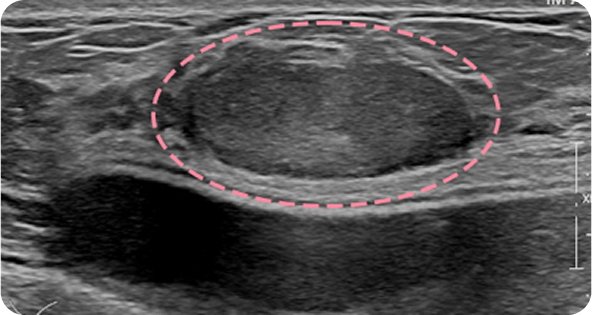

초음파 보면서

맘모톰도 안전하게

양성 종양은 여러 개가 동시에 생겨나기도 합니다. 정상적인 유방 조직 보전에 신경 쓰며 맘모톰 시술을 섬세히 진행했고, 6개월 뒤 추적 관찰을 위한 유방초음파에서 종양이 깨끗이 제거된 것을 확인 했습니다. 일부 반흔 조직은 자연스럽게 호전될 것으로 보여 좋은 예후가 기대되었습니다.